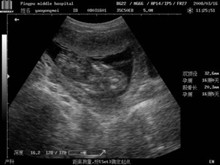

胎死不下

胎死不下是指胎死胞持续时间过长,不能自行输出的人,又称胎死胞胎死不能出。本病相当...

血常规、尿液检测、盆腔及阴道B超、粪便检测、性激素六项、妇科检查